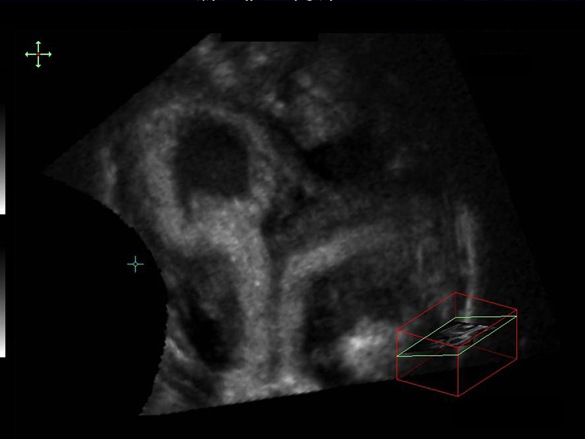

Utérus cloisonné total (œuf clair)